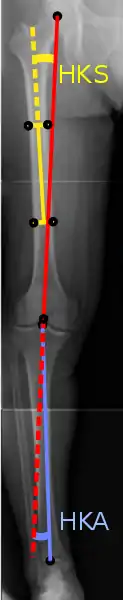

Рентгенографія

На проекційній радіографії, ступінь варусної або вальгусної деформації може бути визначена кількісно за допомогою кута стегна до коліна-щиколотки[6], який представляє собою кут між механічної віссю стегна та центром гомілковостопного суглоба[7]. Зазвичай він становить від 1,0 ° до 1,5 ° вальгусної деформації у дорослих[8]. Нормальний діапазон у дітей різний[9].